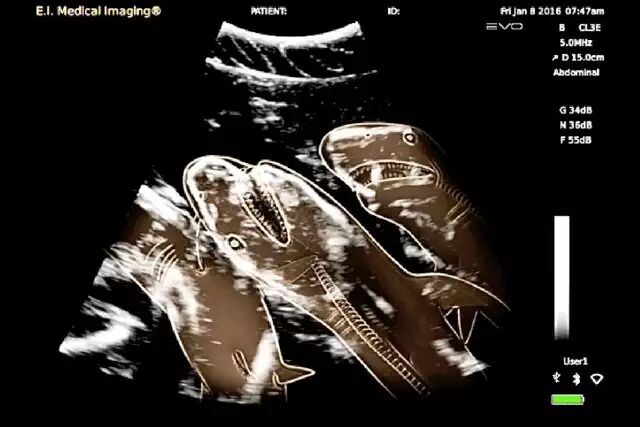

怀孕是一件神圣而又带有神秘色彩的事,她预示着新生命的来临。在动物世界,怀孕是怎样的一种奇迹,以下 14 种动物在怀孕期间的 X 线图片,我们可以通过全新的影像视角探查一番。

• 鲨鱼(为超声图片)